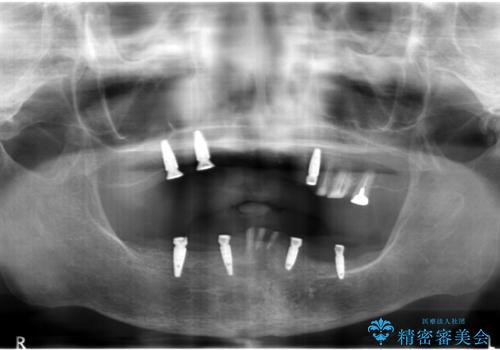

インプラントオーバーデンチャー 咬合平面の改善

- 他院にて入れ歯を入れたが全体的に左に傾いており、咬みにくく、見た目も気になるといらっしゃった方の症例です。

診査の結果、虫歯が進行し保存できない歯が多かったため抜歯し、磁性アタッチメントを用いたインプラントオーバーデンチャーによる咬合及び見た目の改善を行いました。